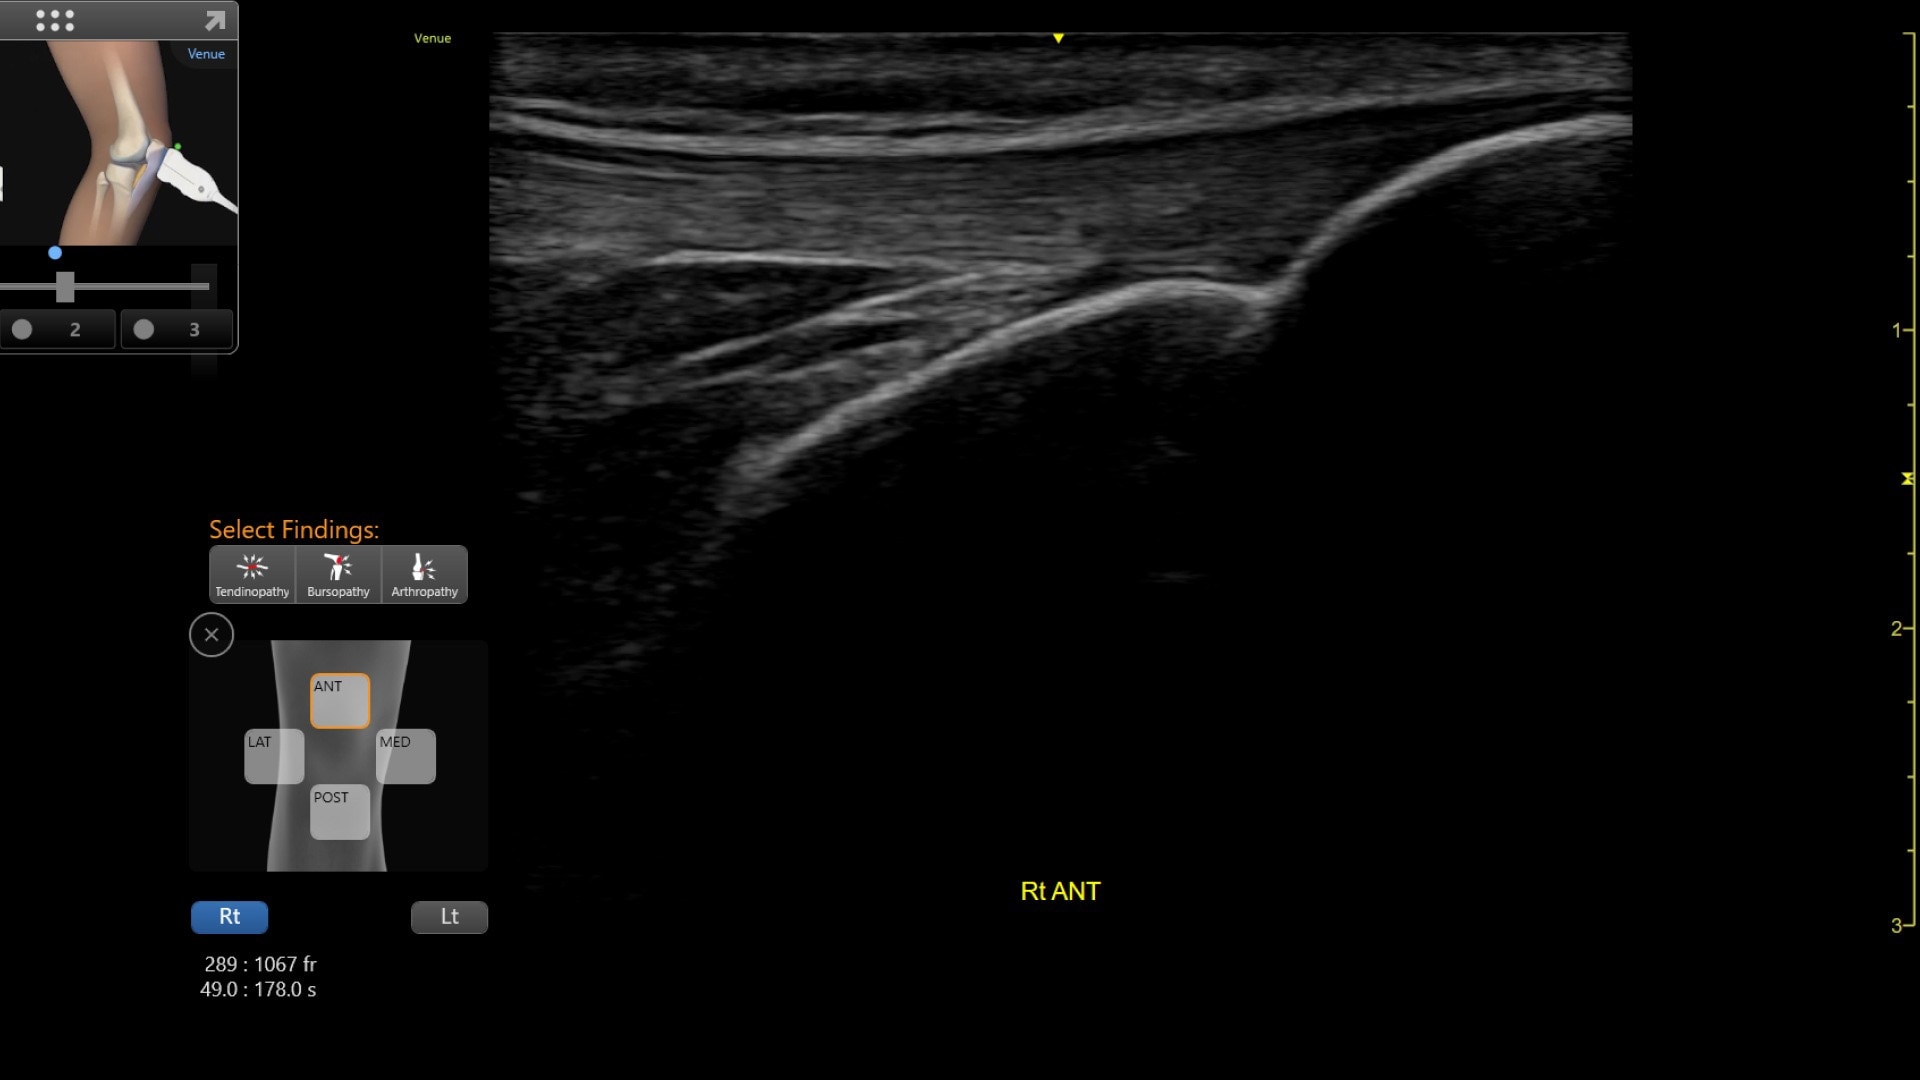

Venue coach MSK

Simplifying MSK scans

This easy-to-use exam documentation tool assists users through exams by providing reference images and anatomy markups. Multiple anatomical areas and helpful video tutorials help clinicians to acquire the scans they need.

MSK Diagrams: Simplifies documentation and assists the clinician in follow up for patients. No need to manually type findings—you can simply assign a label from a pre-populated list that correlates with the images. Get a single view diagram with one click image storing, keep track of assessments and show trends in response to therapy.

Reference Image: Reference image provides anatomy mark-ups to assist novice users in scanning the correct anatomy

Bilateral mode: Helps you to view the opposite side of the same zone for comparison (available for Shoulder preset)